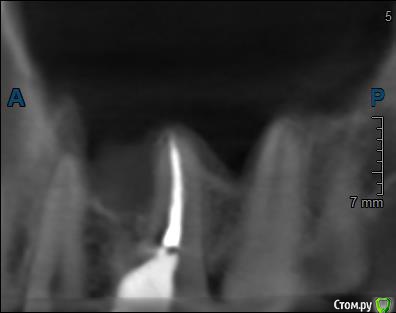

Здравствуйте! Верхний правый шестой зуб пломбировали 3 месяца назад. Примерно месяц назад он начал ныть, после насморка, сначала периодами, а теперь почти постоянно. При постукивание (ощущается не совсем так, как другие зубы) и пальпации десны он не болит. 2,5 месяца назад удаляли кисту из гайморовой пазухи. Может ли быть это какое-то воспаление и есть ли вероятность устранить его какими-нибудь антибиотиками, если да, то как, или может удалить зуб? Если есть воспаление, то какие могут быть последствия если не удалить зуб?

(Снимки с КТ, первые 8(Image) - сделаны сейчас,по 4 в разных проекциях, вторые 8(Before) - сделаны 5 месяцев назад до удаление кисты и повторного пломбирование зуба( до повторного пломбирование он реагировал на горячее, был запломбирован 3 года))

переличили зуб адекватно, во всяком случае по снимкам